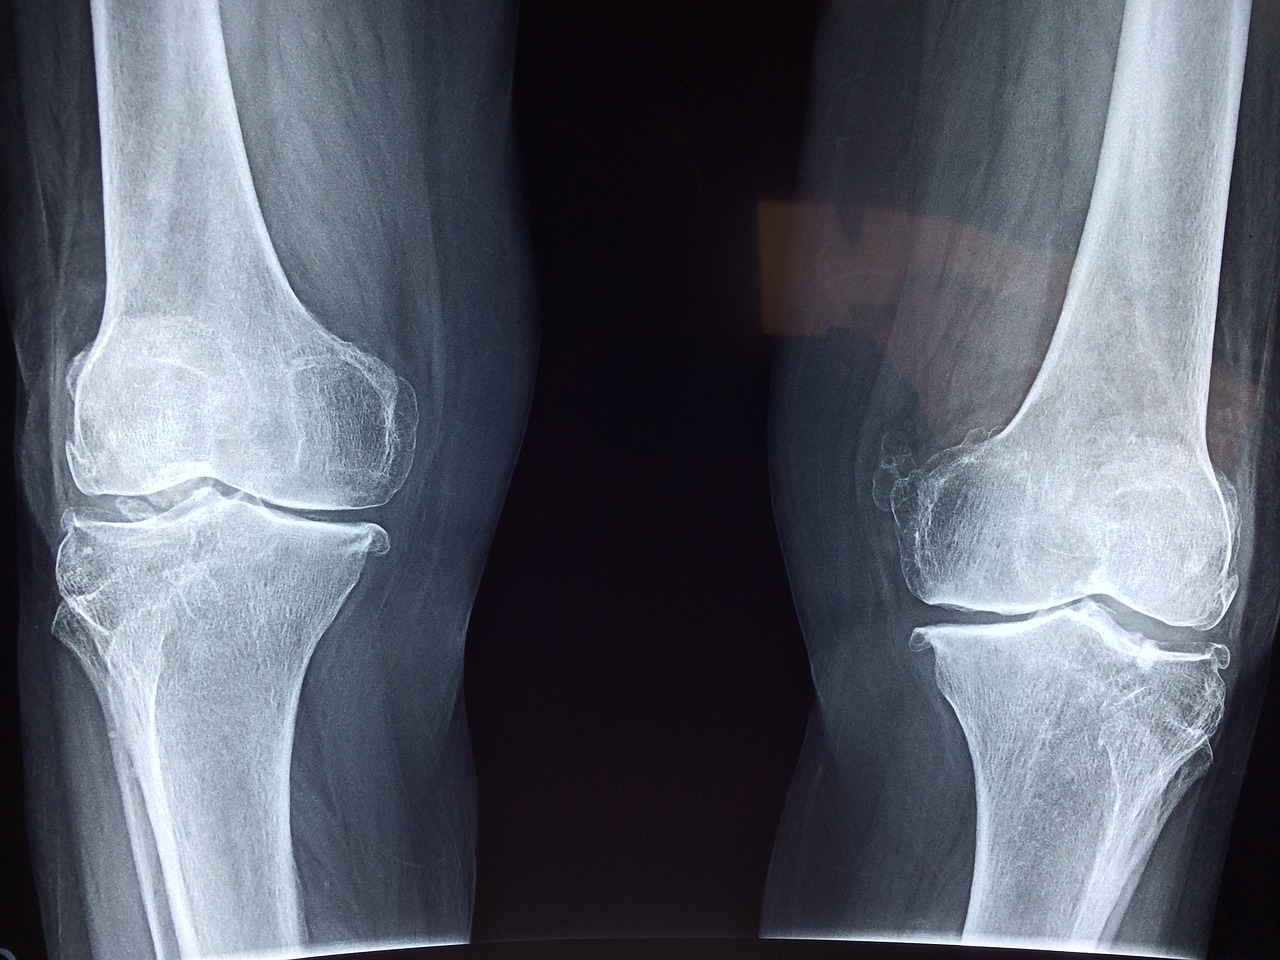

혹시 관절이 너무 안좋아서 제대로 걷지 못하거나 손가락을 움직이지 힘드신 적있으신가요.

관절은 평생 사용하면서 닳아가는 것이기 때문에 관리가 중요합니다.

무릎과 손가락 관절에 좋은 영양제